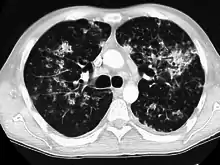

High-resolution CT image showing ground-glass opacities in the periphery of both lungs in a patient with COVID-19 (red arrows). The adjacent normal lung tissue with lower attenuation appears as darker areas.